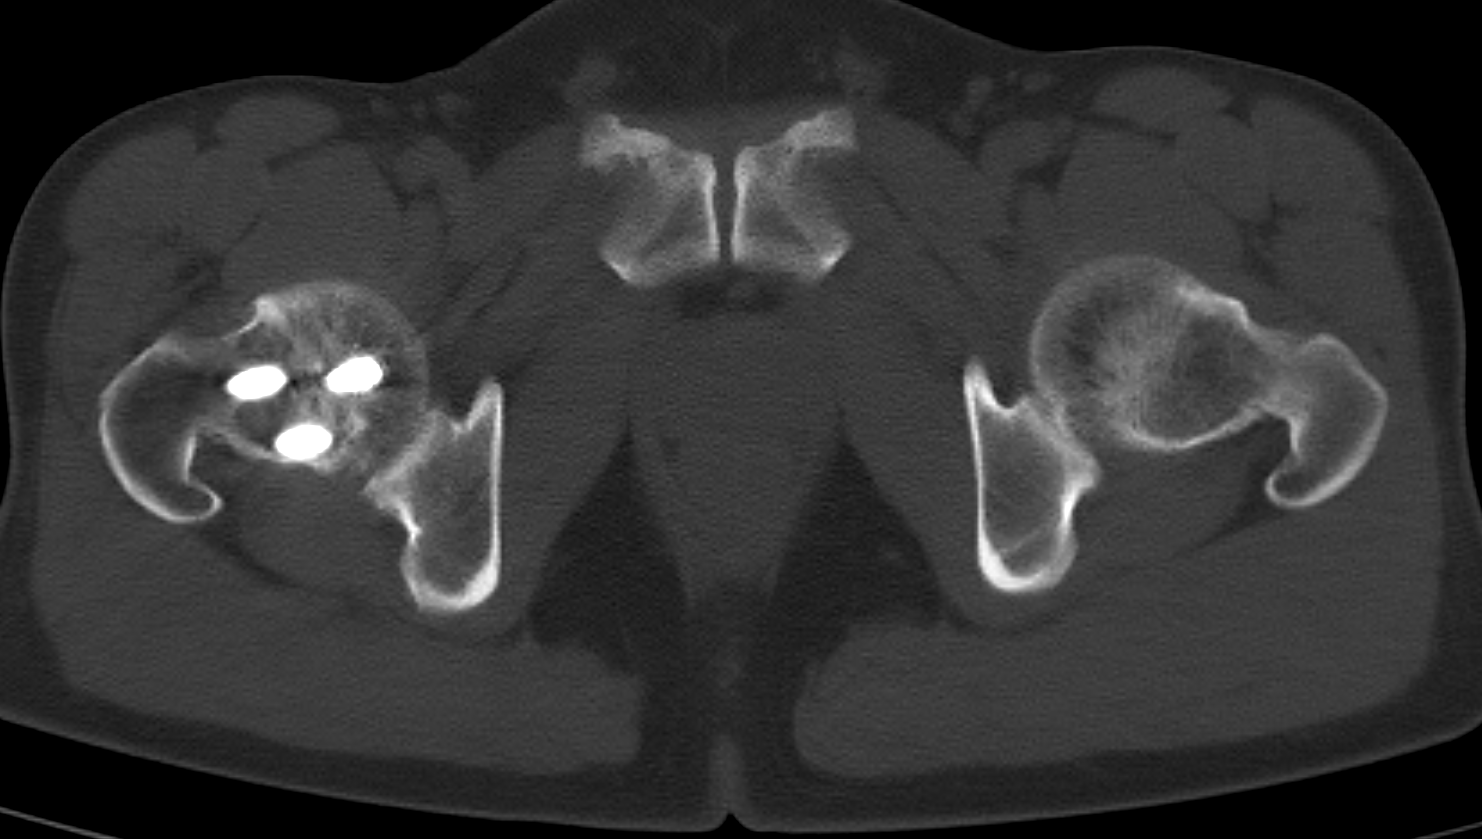

One of the most common uses of a CT scan machine is evaluating trauma and injuries, particularly those affecting bones, joints, and soft tissues.

A CT scan machine can reveal:

Fractures

A CT scan machine is essential for quickly assessing fractures — such as broken ribs, skull fractures, or spinal injuries — from traumas like car accidents or falls. It provides detailed images that can reveal breaks invisible on traditional X-rays, which help doctors see if bones are displaced or if nearby tissues (like muscles or nerves) are damaged.

Joint Disorders

A CT scan provides detailed images that are crucial for diagnosing joint-related conditions such as arthritis, degenerative changes, and bone spurs — all potential sources of pain and restricted mobility. By clearly revealing the extent of damage within the joint, it enables clinicians to accurately assess severity and make informed decisions regarding treatment, whether that involves physical therapy, medication, or surgical intervention.